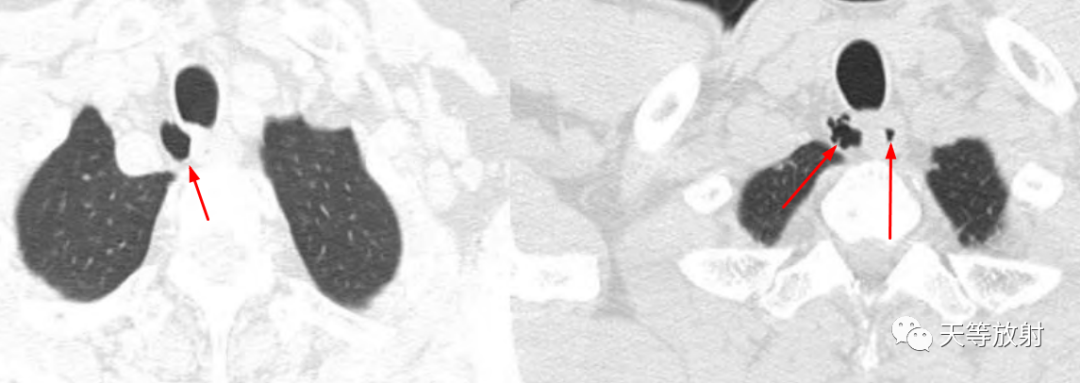

薄层CT并放大观察,胸廓入口处气管旁纵隔内局限含气影,可见细线样低密度影与气管交通。

冠状位及矢状位观察,囊影位于胸廓入口右侧旁。